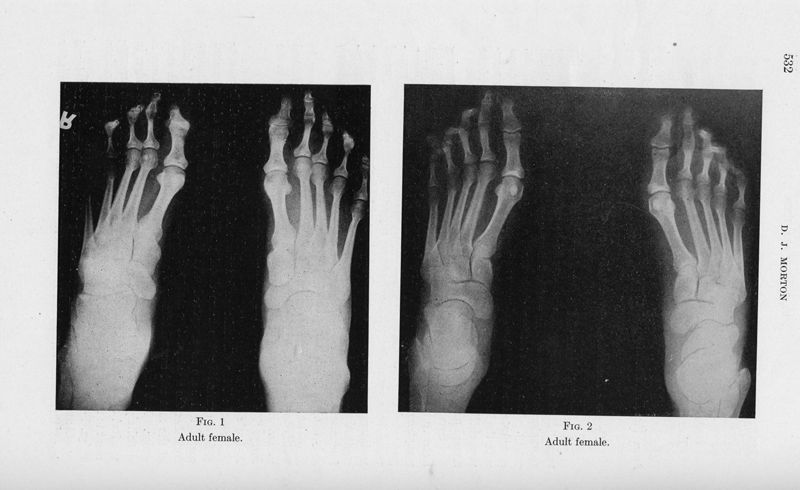

MORTON, Dudley J.

Metatarsus atavicus. The identification of a distinctive type of foot disorder

In : [The] Journal of bone and joint surgery, 1927, Vol. 9, pp. 531-44